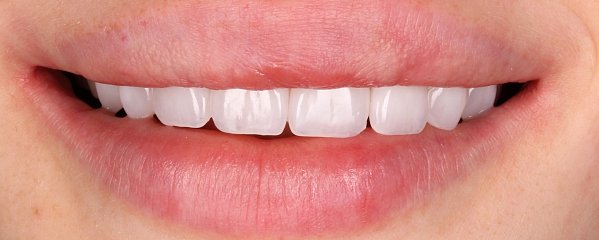

Пациентка обратилась по эстетическим показаниям, изначально у нее выявлено: недостаточная ширина улыбки, снижение высоты нижней трети лица, отсутствие плотного смыкания зубов в боковом отделе, сужение зубных рядов. Так же пациентка была очень недовольна формой и цветом передней группы зубов. Был поставлен диагноз — Мезиальная окклюзия. Сужение зубных рядов. Нарушение эстетики.

Основные пожелания пациентки — иметь ровный зубной ряд с правильным смыканием и положением зубов, но

Что было сделано:

-

Выровняли дугу улыбки с помощью

брекет-системы и техники многопетлевых дуг. - Провели коррекцию соотношения челюстей, добились нормализации формы и размеров зубных рядов.

- В области передней группы зубов были оставлены промежутки, для возможности увеличения размеров зубов

- Ортопедом фиксированы цельнокерамические виниры. Цвет и форма подбирались совместно с пациентом.

В итоге зубы стали не просто ровными, а идеальными: по форме и размерам. И цвет- главное пожелание пациентки — ослепительно белый! Результат на лицо!

Комплексный план лечения реализовала команда врачей: ортодонт Десяткина А.В., ортопед Десяткин И.М.